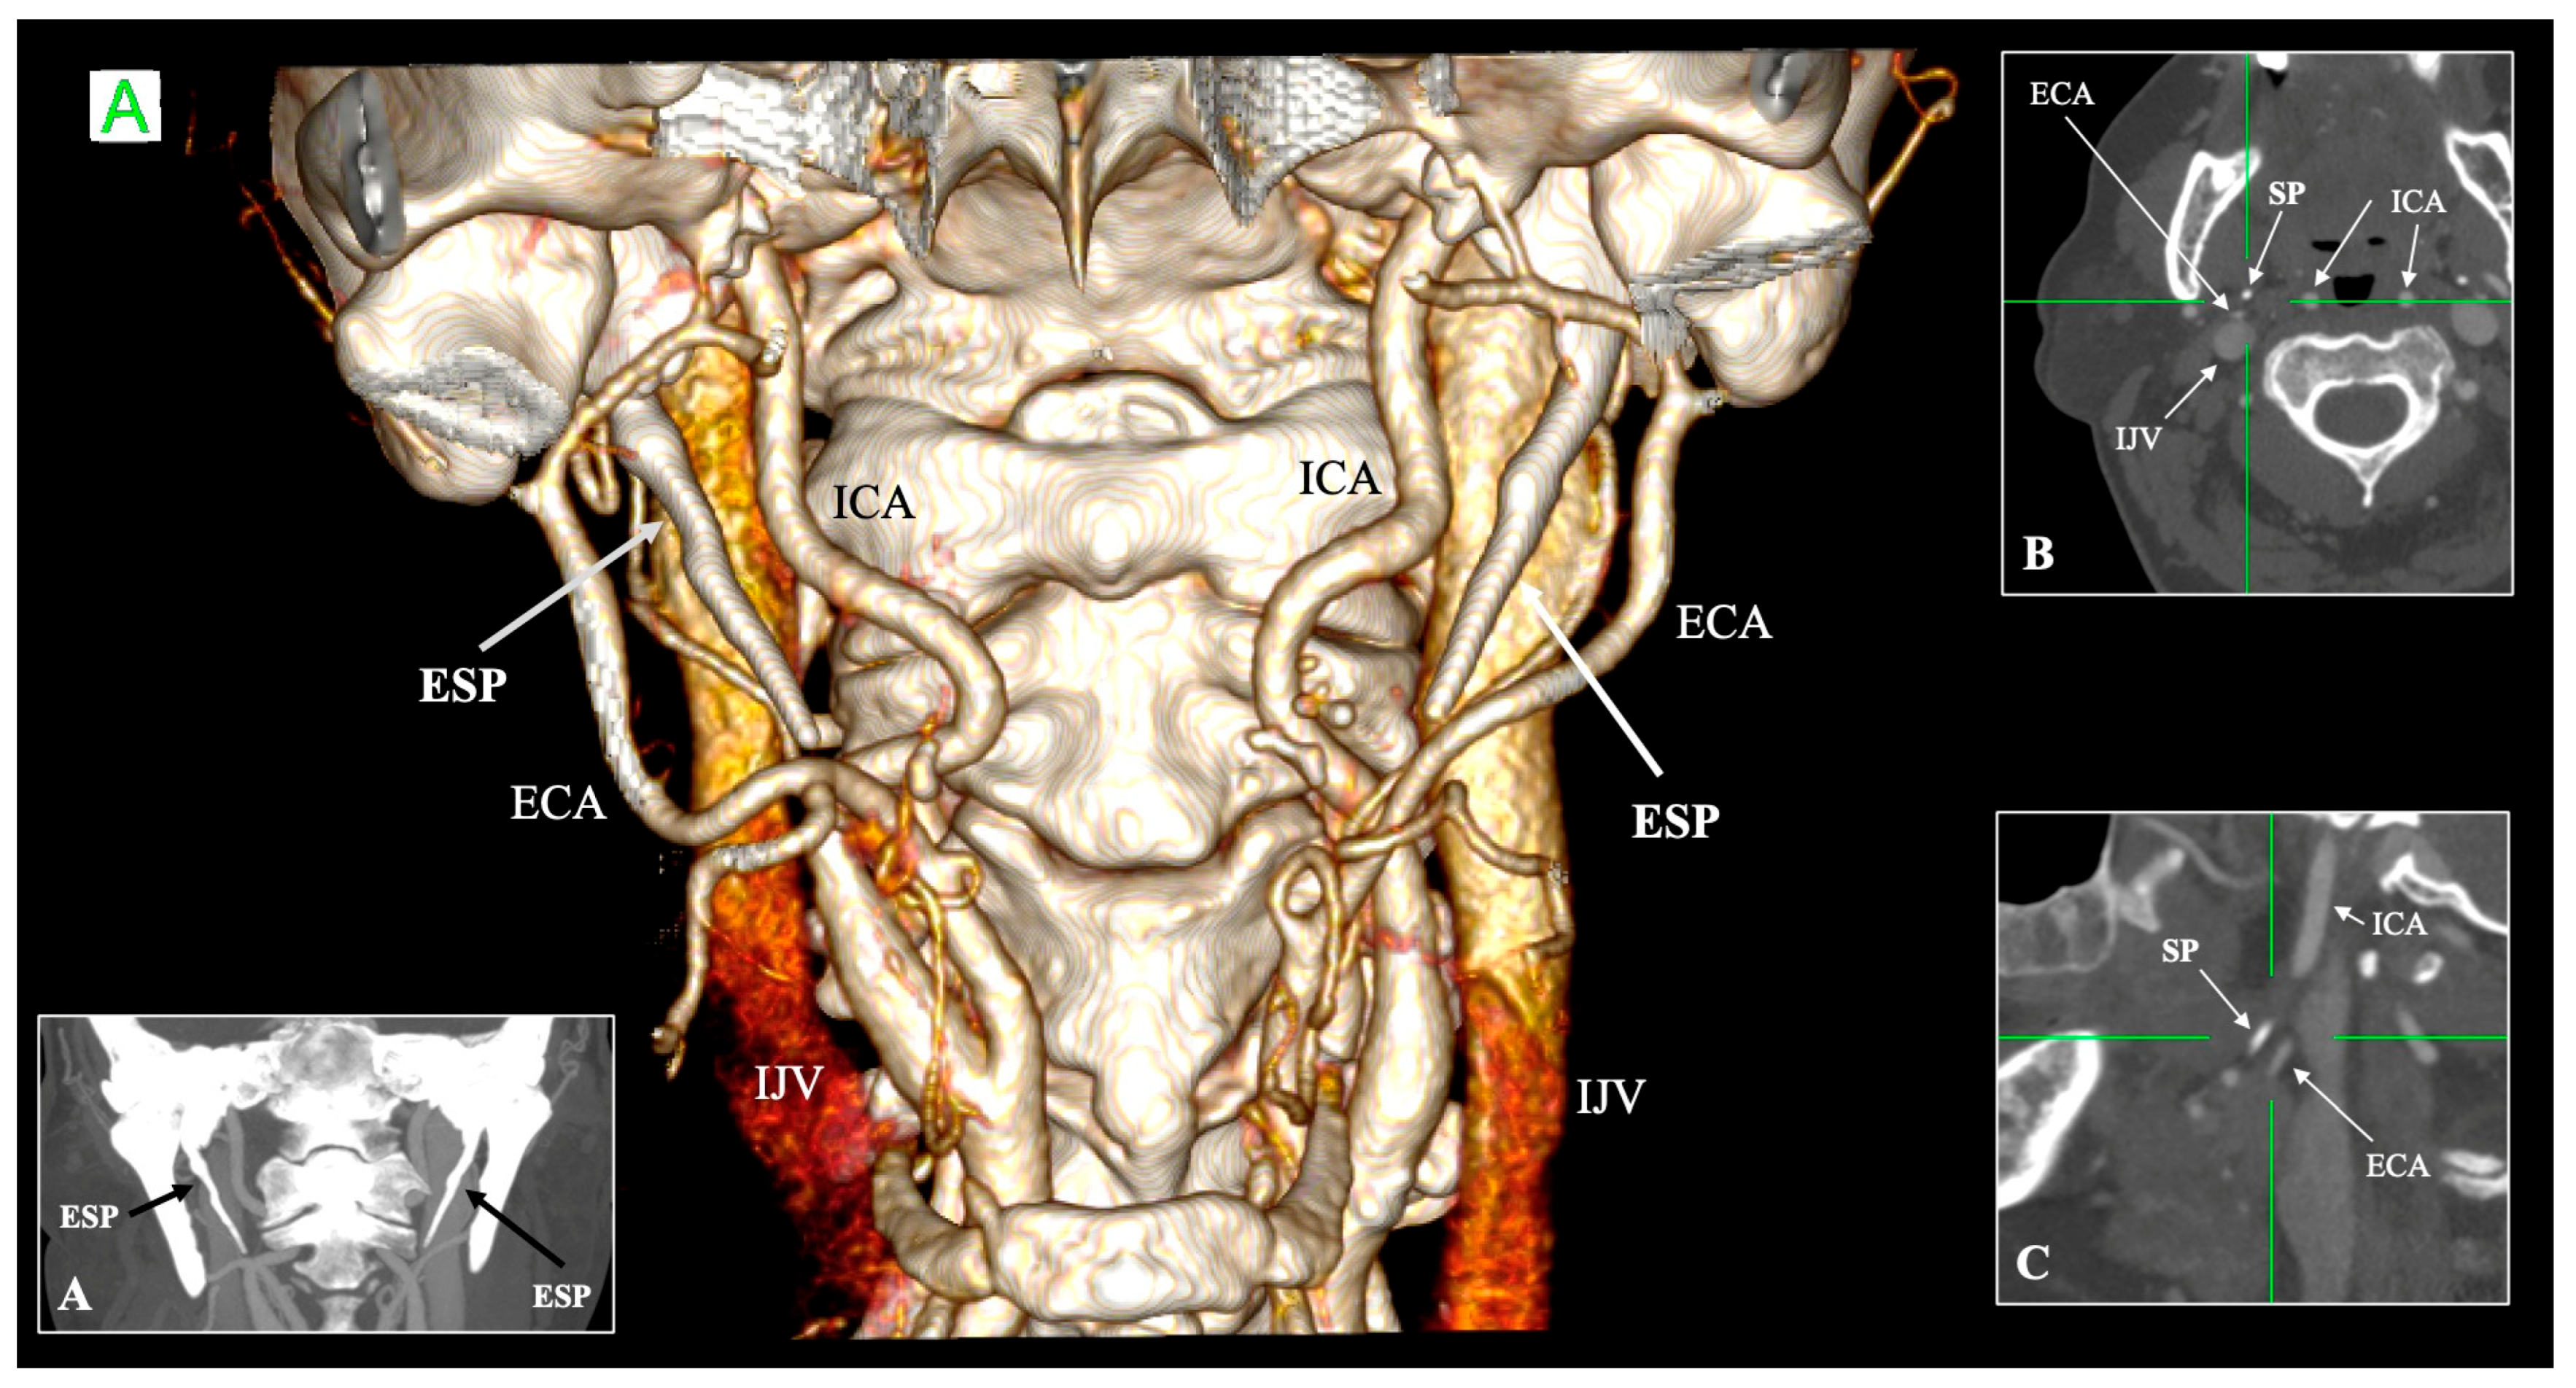

- Jugular variant (Eagle jugular syndrome): Zamboni et al. [55] described compression of the IJV between the SP and the C1 transverse process, producing intracranial hypertension, papilledema, venous congestion, and even peri-mesencephalic hemorrhage [55]. Headache and orbital symptoms dominate, distinguishing it from the carotid subtype [56].

- Triantafyllou, G.; Botis, G.; Vassiou, K.; Vlychou, M.; Tsakotos, G.; Kalamatianos, T.; Matsopoulos, G.; Piagkou, M. Τhe Styloid Process Length and the Stylohyoid Chain Ossification Affect Its Relationship with the Carotid Arteries. Ann. Anat. Anat. Anz. 2025, 257, 152342. [Google Scholar] [CrossRef] [PubMed]

- Triantafyllou, G.; Papadopoulos-Manolarakis, P.; Vassiou, K.; Vlychou, M.; Karangeli, N.; Papanagiotou, P.; Tsakotos, G.; Piagkou, M. The Impact of the Styloid Process Angulation on the Carotid Arteries. Ann. Anat. Anat. Anz. 2025, 258, 152378. [Google Scholar] [CrossRef]

| Internal carotid artery (ICA) | Medial to SP, ascends branchless to the skull base | Tortuosity, kinking, coiling; reduced ICA–SP distance; direct bony contact | Risk of dissection, ischemic stroke, and hemorrhage during pharyngeal surgery | Paulsen et al. [14]; Renard et al. [47]; Raser et al. [45]; Amorim et al. [46] |

| External carotid artery (ECA) | Anterolateral to SP; gives facial and pharyngeal branches | Retro-styloid course (~9–12%) | Altered surgical corridor; potential compression or irritation | Karangeli et al. [17]; Calotă et al. [50] |

| Internal jugular vein (IJV) | Posterolateral to SP within the carotid sheath | Compression between SP and C1 transverse process (“jugular nutcracker”) | Intracranial hypertension, venous congestion, hemorrhage | Triantafyllou et al. [48] |